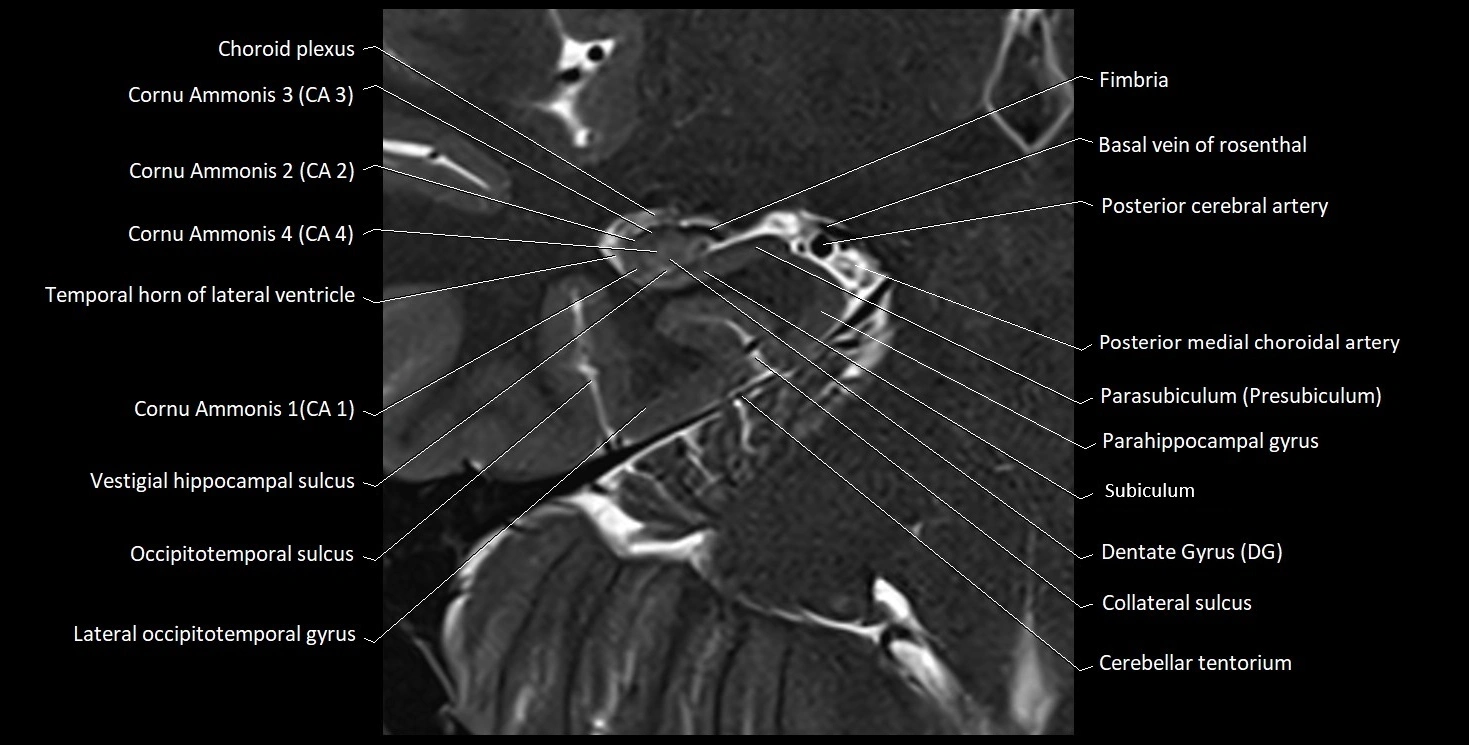

MRI Appearance

T1-weighted images:

• Alveus: Thin linear high signal band (due to myelinated fibers) overlying the hippocampal gray matter.

• Hippocampal gray matter: Intermediate signal intensity.

• CSF of lateral ventricle: Dark (low signal).

• Pathology:

• Sclerosis: Alveus becomes indistinct, with reduced T1 signal and hippocampal atrophy.

• Edema or gliosis: Diffuse hypointensity and blurring of alvear margins.

T2-weighted images:

• Alveus: Low signal line overlying brighter hippocampal gray matter.

• CSF: Bright hyperintense.

• Gliosis or demyelination: Causes increased signal in the alvear region.

• Hippocampal sclerosis: Gray-white differentiation becomes indistinct.

• Edema: Hyperintense change surrounding alveus.

MRI images

image